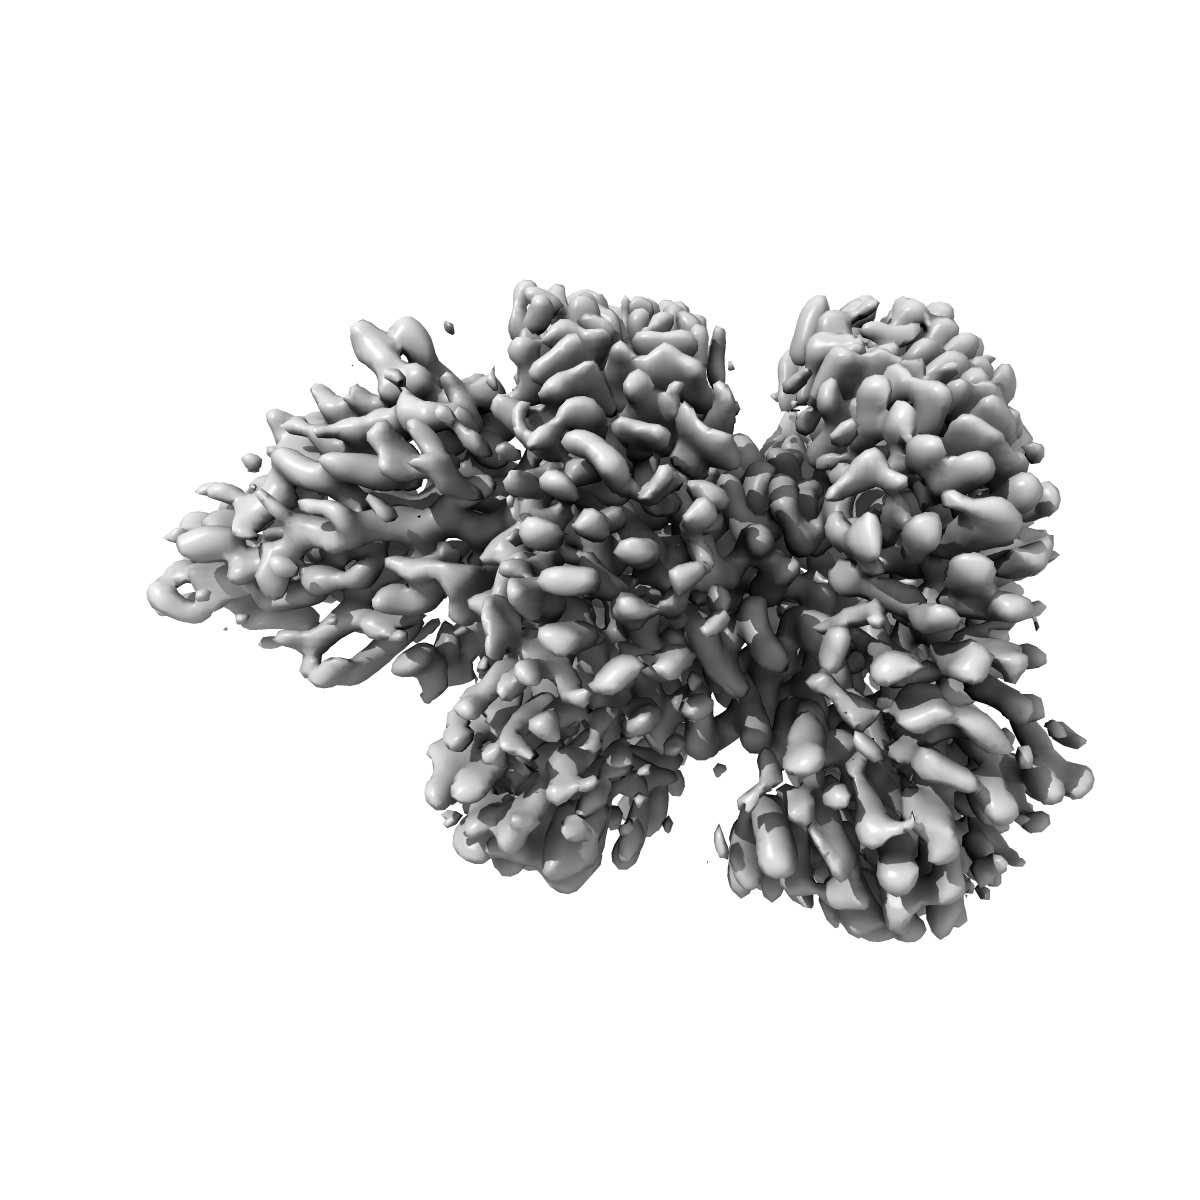

Cryo-EM structure of the proton coupled folate transporter at pH 6.0 bound to pemetrexed

Single-particle3.3 Å

Sample: Complex of the proton coupled folate transporter at pH 6.0 bound to pemetrexed

Structural basis of antifolate recognition and transport by PCFT.

(2021) Nature , 595 , 130 - 134